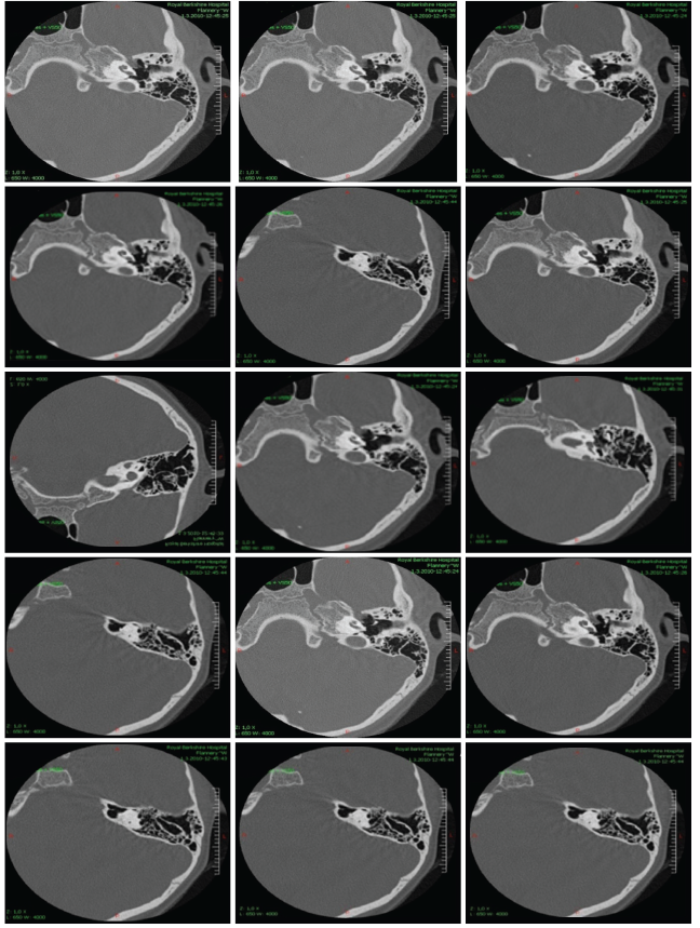

We are presenting three of our patients with this rare syndrome. First, we present a girl, aged four years at diagnosis, who has fulfilled BOR diagnostic criteria manifesting three cardinal features: unilateral renal hypoplasia, bilateral cervical branchial cysts and a hearing loss. Family history was negative for hearing loss, neck fistula and kidney problems. She has a younger healthy brother. She has achieved regular milestones, except development of speech, which was delayed and non-intelligible for the unknown listeners. Her intelligence and growth were normal at the age of four years. In-utero presence of unilateral renal hypoplasia was noticed. Lateral fistula on the left neck-side was operated on at the age of three years. Preauricular pits were present on both sides. Otoscopic and rhinoscopic findings were regular bilaterally. Throat was showing velopharyngeal insufficiency without having signs of submucous cleft palate as a minor criteria. Tympanogram was type A on both sides and acoustic reflex was absent bilaterally at all probe intensities. Transient otoacoustic emissions were not registered. Tonal audiometry showed a conductive hearing loss bilaterally with pure tone average about 75 dB for air conduction. Brainstem evoked auditory potentials confirmed this finding. Caloric test showed regular function of the both labyrinths. Computerised tomography of temporal bones confirmed malformations in both middle ears (Figure 1). Genetic investigations in the UK have confirmed the presence of BOR syndrome registering the EYA 1 mutation at 8q chromosome (Figure 2).

Figure 1: Audiology findings belonging to a four year old girl with Branchio Oto Renal syndrome

who has conductive hearing loss (some images scanned from originals).

Figure 2: Computerised tomography of temporal bones belonging to a four year old girl with Branchio Oto Renal

syndrome who has conductive hearing loss as a conseqence of ossicle malformations.